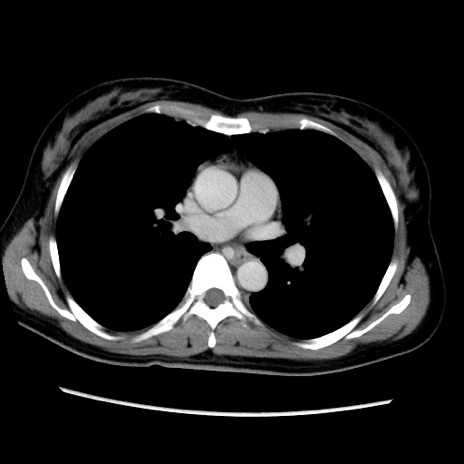

症例39(横断像)

【症例】40歳代女性

【主訴】上下腹部痛

【現病歴】2日目から下腹部痛あり。夜間は痛みで眠れなかった。昨日より上腹部痛と下痢が出現。臥位で痛みは軽快したため、休んでいた。本日になって臥位でも立位でも痛みが強くなってきたため救急要請。

【既往歴】子宮内膜症

【身体所見】部:平坦・軟、左上下腹部に圧痛あり、反跳痛あり。

【データ】WBC 21800、CRP 26.78